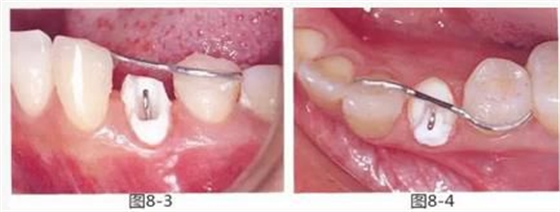

圖8-3 使用方絲和鏈狀橡皮圈,通過(guò)正畸的手段挺出牙齒。

圖8-4 使用粘接性樹(shù)脂,將S狀方絲固定在鄰牙上。